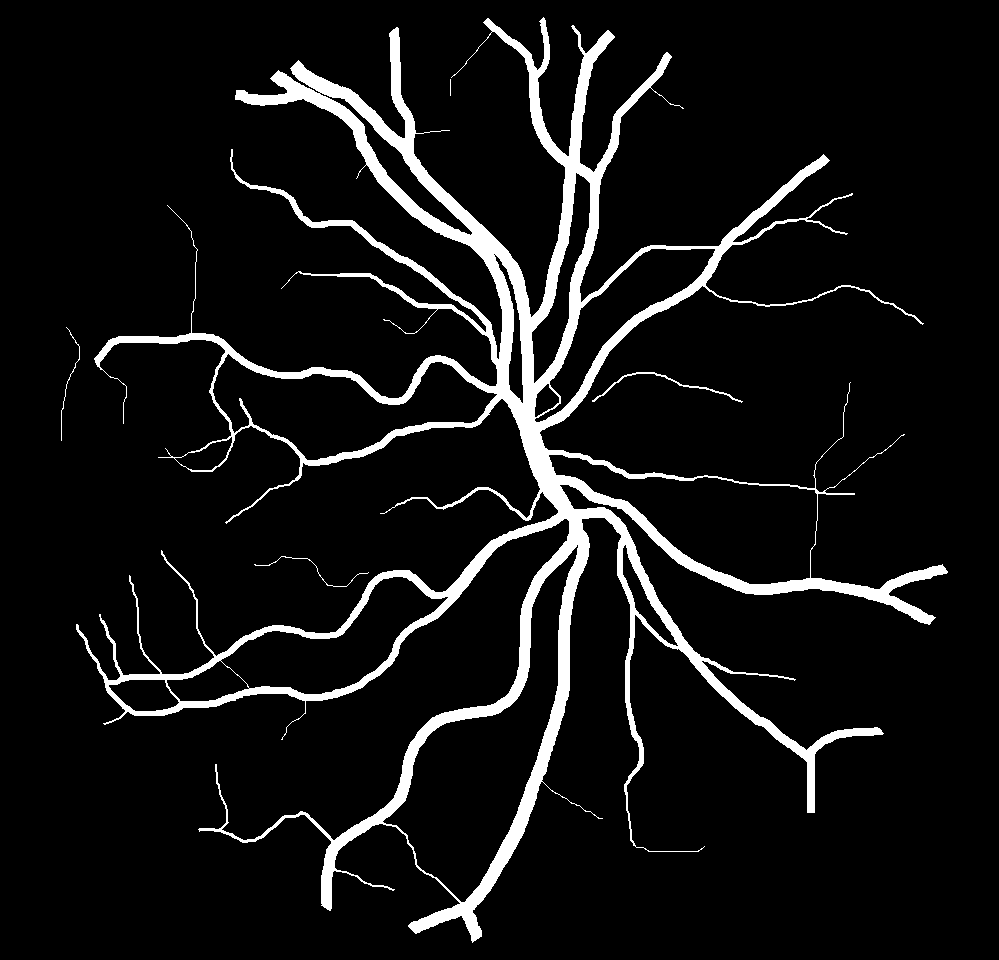

Table VI presents a quantitative comparison of the measured diameters using the segmentation outputs of SegRAVIR and competing approaches. Using the pixel-wise annotated masks, the reference average diameter of the arteries and veins in the test set of the RAVIR dataset were measured as and , respectively. According to our analysis, SegRAVIR can accurately measure the diameter of the vessels and it achieves the smallest MAPE among the competing approaches. Specifically, in comparison to CE-Net, Iter-Net, and DU-Net, respectively, SegRAVIR is on average , and more accurate in terms of MAPE for the measured diameter of arteries and , and in terms of MAPE for the measured diameter of veins. Fig. 6 presents qualitative comparisons of reference and SegRAVIR estimated diameter maps.

(a) (b) (c)